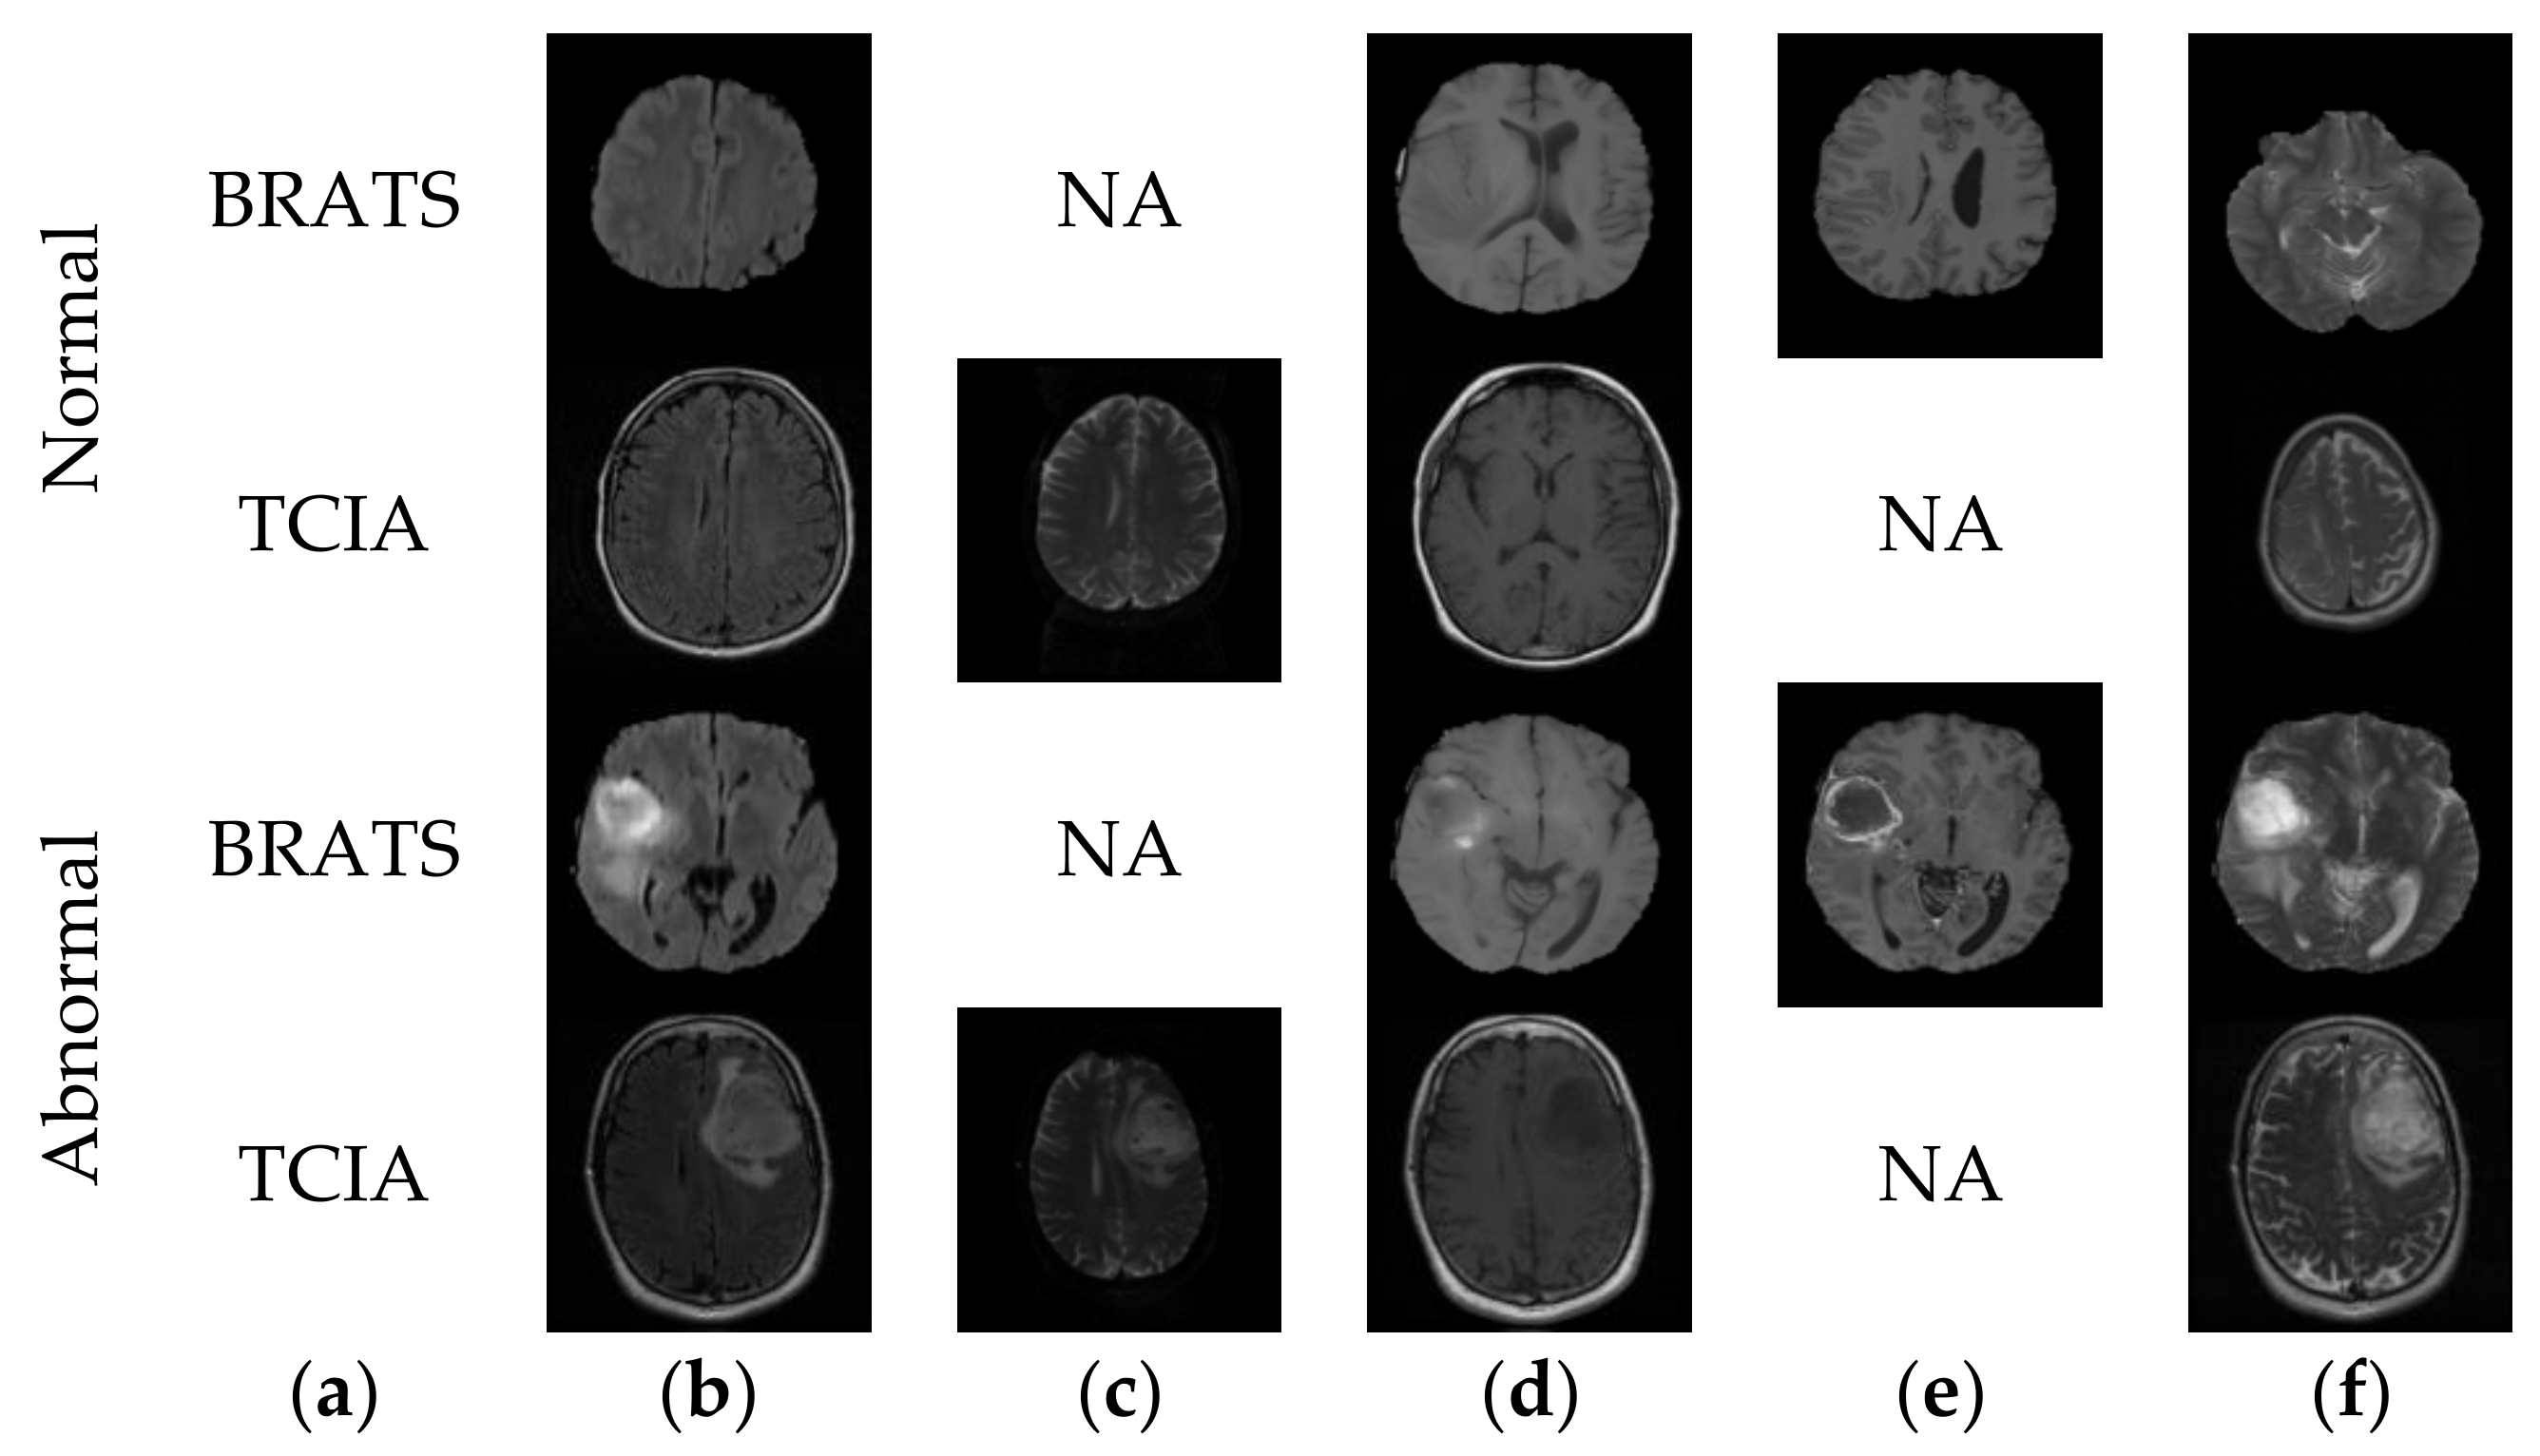

| Image Class | Modality | Number of Images for Training | Number of Images for Testing |

|---|---|---|---|

| Normal (BRATS+TCIA) | Mixed (Flair+T2) | 1000 | 400 |

| Abnormal (BRATS) | Flair | 1500 | 600 |

| T2 | 1500 | 600 | |

| T1C | 1500 | 600 | |

| Abnormal (TCIA) | T2 | 1000 | 400 |

| Abnormal (Clinical) | T2 | 200 | 200 |